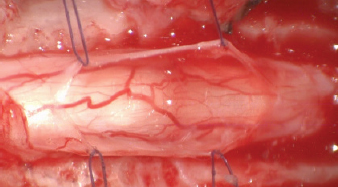

The following data were recorded for each dog: signalment, clinical history, clinical and neurological examinations, magnetic resonance imaging (MRI) findings, confirmed diagnosis after surgical exploration, standardized surgical procedure, and outcome at least 6 months after surgery. Dogs were anaesthetized according to the standard ethics procedure using anesthetic medications. MRI of the spinal cord was acquired under general anesthesia in dorsal recumbency using low-field MRI scanners (Hitachi aperto grande 0.4T; Esaote Vet Grande, Genova, Italy). Interpretation of the images was obtained in seven dogs by a board-certified radiologist and in one dog by a neurology clinician. All spinal surgeries were performed using a surgical microscope (Zeiss NC-2). A dorsal laminectomy approach was taken in all cases by removing the dorsal lamina over the SAD and preserving the articular facets joints (Funkquest, type B). This approach permitted a good visualization of the dorsal spinal cord, allowing the performance of a longitudinal durotomy with a no. 11 blade and microsurgical Castroviejo scissors (Fig. 1). The durotomy was extended cranially and caudally to the SAD until normal spinal cord was exposed. Stay sutures were then applied at the dural edges and maintained in place with small hemostats using a polydioxanone 6-0 (Ethicon LLC, San Lorenzo, PR) (Fig. 2). This technique exposed the SAD allowing the visualization of the subarachnoid diverticulum, subarachnoid CSF accumulation, and surrounding adhesions, most of which were microsurgically removed (Figs. 35). The stay sutures were not used for dural closure, and the holes of the stay sutures were incorporated into the durotomy repair. In all cases, the dural closure was completed using a simple continuous pattern with polydioxanone 6-0 (Ethicon LLC, San Lorenzo, PR) in seven dogs and with polyamide 5-0 (Ethicon LLC, San Lorenzo, PR) in one dog; waterproof suture was achieved by noting the absence of CSF leakage (Fig. 6). No dural patch or autologous material was placed over the laminectomy defect. The muscular, subcutaneous, and skin layers were routinely closed. The Glasgow modified pain score system was utilized for the postoperative provision of analgesia. Dogs were hospitalized until good pain management was achieved with oral medication and satisfactory movements of pelvic limbs were observed. Outcome was deemed unsuccessful if there was progressive neurological deterioration and successful if the neurological signs were similar or improved compared to the neurological signs at presentation. Short-term and long-term outcomes were defined as less than 7 months and more than 7 months. Follow-ups were evaluated by neurological examination by the authors in the same institution where the spinal surgery was performed or by custom-designed telephone questionnaire used by Alisauskaite et al. (2019), along with a video evaluation of the dog sent via email from the owner. In addition, owner’s level of satisfaction regarding the neurological improvement was recorded.

Fig. 5. Spinal cord free form adherences and CSF flow restored.

Fig. 6. Closure of the durotomy.